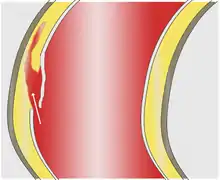

As with all other arteries, the aorta is made up of three layers, the intima, the media, and the adventitia. The intima is in direct contact with the blood inside the vessel, and mainly consists of a layer of endothelial cells on a basement membrane; the media contains connective and muscle tissue, and the vessel is protected on the outside by the adventitia, comprising connective tissue.[25]

In an aortic dissection, blood penetrates the intima and enters the media layer. The high pressure rips the tissue of the media apart along the laminated plane splitting the inner two-thirds and the outer one-third of the media apart.[26] This can propagate along the length of the aorta for a variable distance forward or backward. Dissections that propagate towards the iliac bifurcation (with the flow of blood) are called anterograde dissections and those that propagate towards the aortic root (opposite of the flow of blood) are called retrograde dissections. The initial tear is usually within 100 mm of the aortic valve, so a retrograde dissection can easily compromise the pericardium leading to a hemopericardium. Anterograde dissections may propagate all the way to the iliac bifurcation of the aorta, rupture the aortic wall, or recanalize into the intravascular lumen leading to a double-barrel aorta. The double-barrel aorta relieves the pressure of blood flow and reduces the risk of rupture. Rupture leads to hemorrhaging into a body cavity, and prognosis depends on the area of rupture. Retroperitoneal and pericardial ruptures are both possible.[27]

The initiating event in aortic dissection is a tear in the intimal lining of the aorta. Due to the high pressures in the aorta, blood enters the media at the point of the tear. The force of the blood entering the media causes the tear to extend. It may extend proximally (closer to the heart) or distally (away from the heart) or both. The blood travels through the media, creating a false lumen (the true lumen is the normal conduit of blood in the aorta). Separating the false lumen from the true lumen is a layer of intimal tissue known as the intimal flap.

The vast majority of aortic dissections originate with an intimal tear in either the ascending aorta (65%), the aortic arch (10%), or just distal to the ligamentum arteriosum in the descending thoracic aorta (20%).

As blood flows down the false lumen, it may cause secondary tears in the intima. Through these secondary tears, the blood can re-enter the true lumen.

While it is not always clear why an intimal tear may occur, quite often it involves degeneration of the collagen and elastin that make up the media. This is known as cystic medial necrosis and is most commonly associated with Marfan syndrome and is also associated with Ehlers-Danlos syndrome.[28][29]